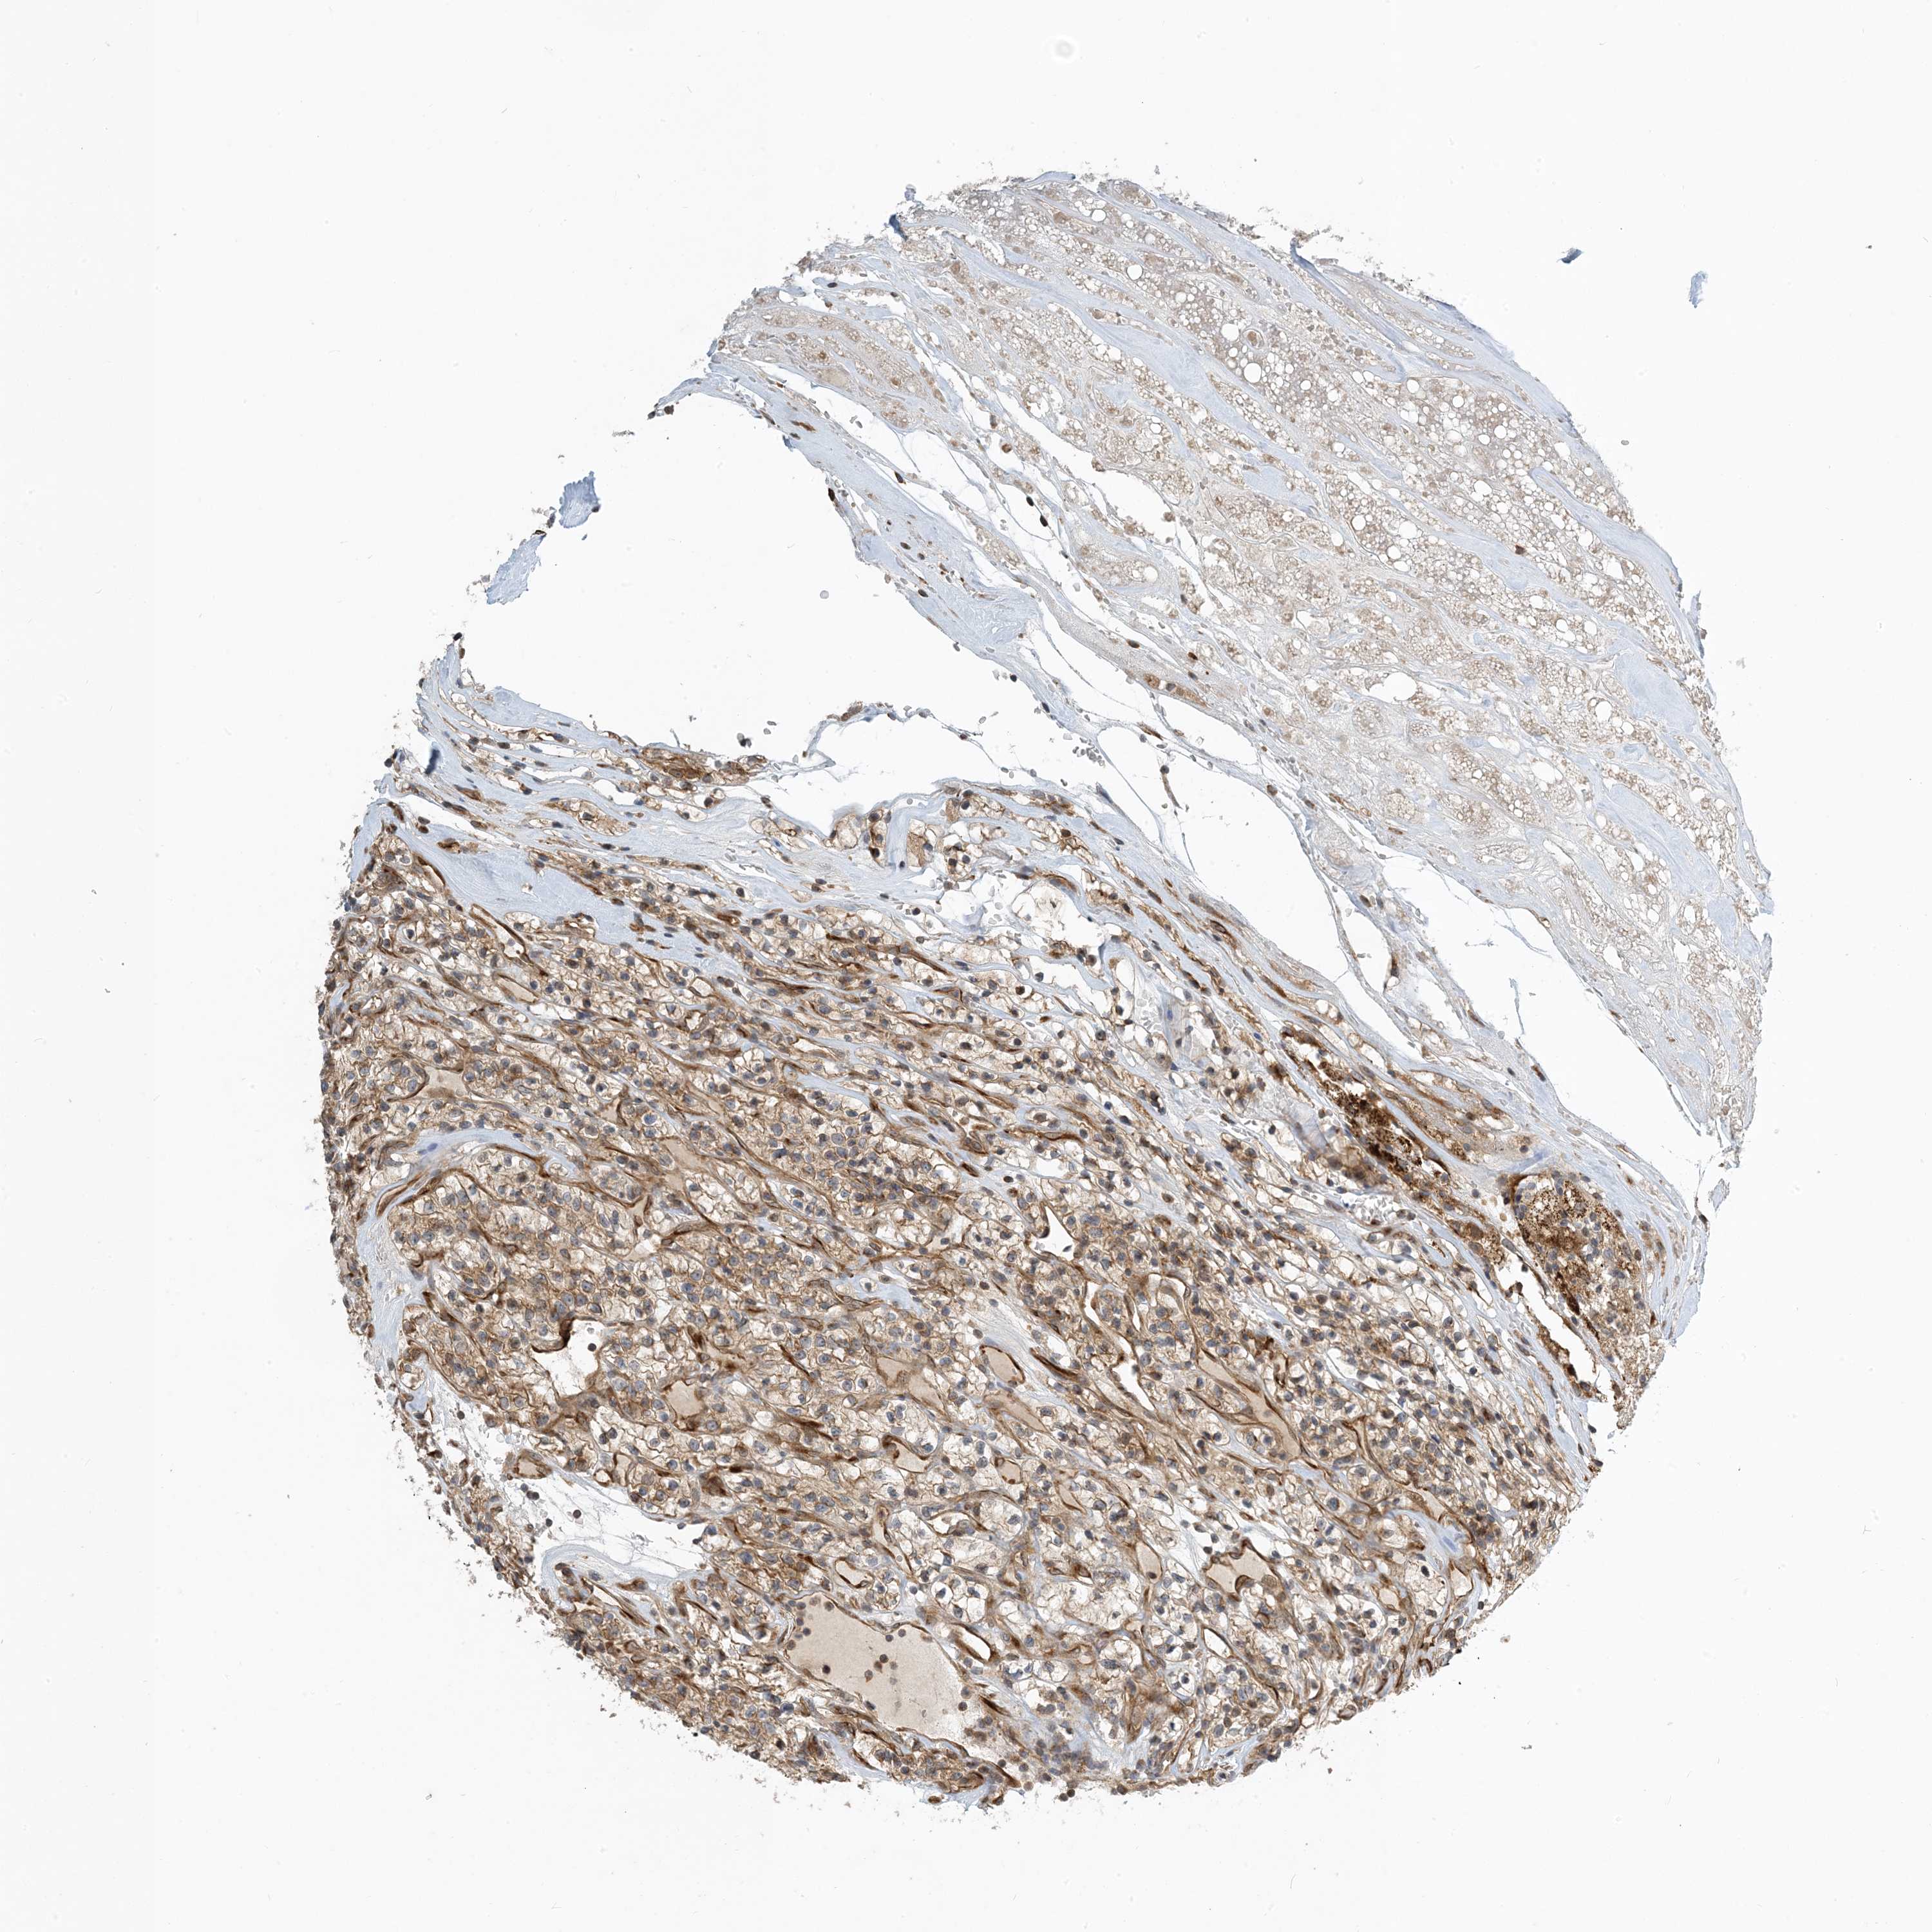

KIDNEY RENAL PAPILLARY CELL CARCINOMA (TCGA) - Interactive survival scatter ploti

The Survival Scatter plot shows the clinical status (i.e. dead or alive) for all individuals in the patient cohort, based on the same data that underlies the corresponding Kaplan-Meier plots. Patients that are alive at last time for follow-up are shown in blue and patients who have died during the study are shown in red.

The x-axis shows the expression levels (FPKM) of the investigated gene in the tumor tissue at the time of diagnosis. The y-axis shows the follow-up time after diagnosis (years). Both axes are complimented with kernel density curves demonstrating the data density over the axes. The top density plot shows the expression levels (FPKM) distribution among dead (red) and alive patients (blue). The right density plot shows the data density of the survived years of dead patients with high and low expression levels respectively, stratified using the cutoff indicated by the vertical dashed line through the Survival Scatter plot. This cutoff is automatically defined based on the FPKM cutoff that minimizes the p-score. The cutoff can be changed by dragging the vertical line or by entering a cutoff value in the square labeled "Current cut-off".

Under the Survival Scatter plot the p-score landscape (black curve; left axis) is shown together with dead median separation (red curve; right axis). Dead median separation is the difference in median mRNA expression between patients who have died with high and low expression, respectively. It is calculated as follows: median FPKM expression of dead patients with high expression - median FPKM expression of dead patients with low expression. This is intended to aid the user in visually exploring custom cutoffs and the associated p-scores and dead median separation.

Individual patient data is displayed and can be filtered by clicking on one or more of the category buttons on the top of the page. Categories describing expression level and patient information include: high, low, alive, dead, female, male and tumor stages. The scale of the x-axis can be toggled between linear and log-scale by clicking on the "x log" button. Mouse-over function shows TCGA ID, patient information and mRNA expression (FPKM) for each patient.

& Survival analysisi

Kaplan-Meier plots summarize results from analysis of correlation between mRNA expression level and patient survival. Patients were divided based on level of expression into one of the two groups "low" (under cut off) or "high" (over cut off). X-axis shows time for survival (years) and y-axis shows the probability of survival, where 1.0 corresponds to 100 percent.

ZBTB3 is potential prognostic, high expression is favorable in Kidney Renal Papillary Cell Carcinoma (TCGA)